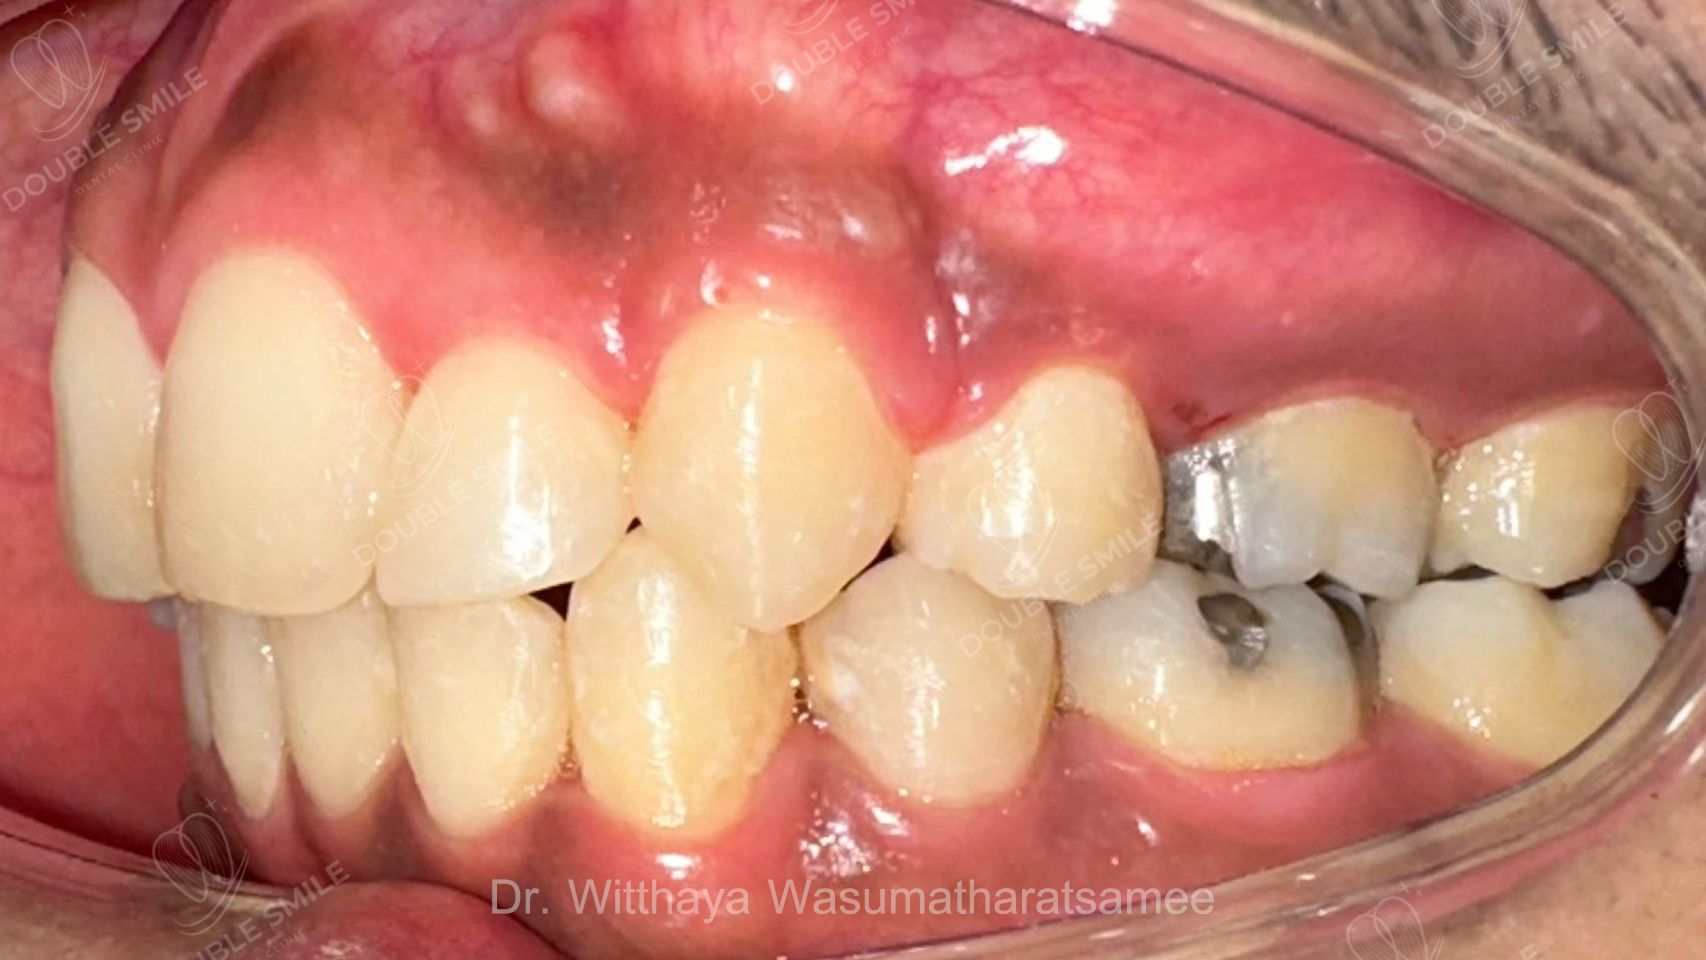

After

Case Review

Before & After